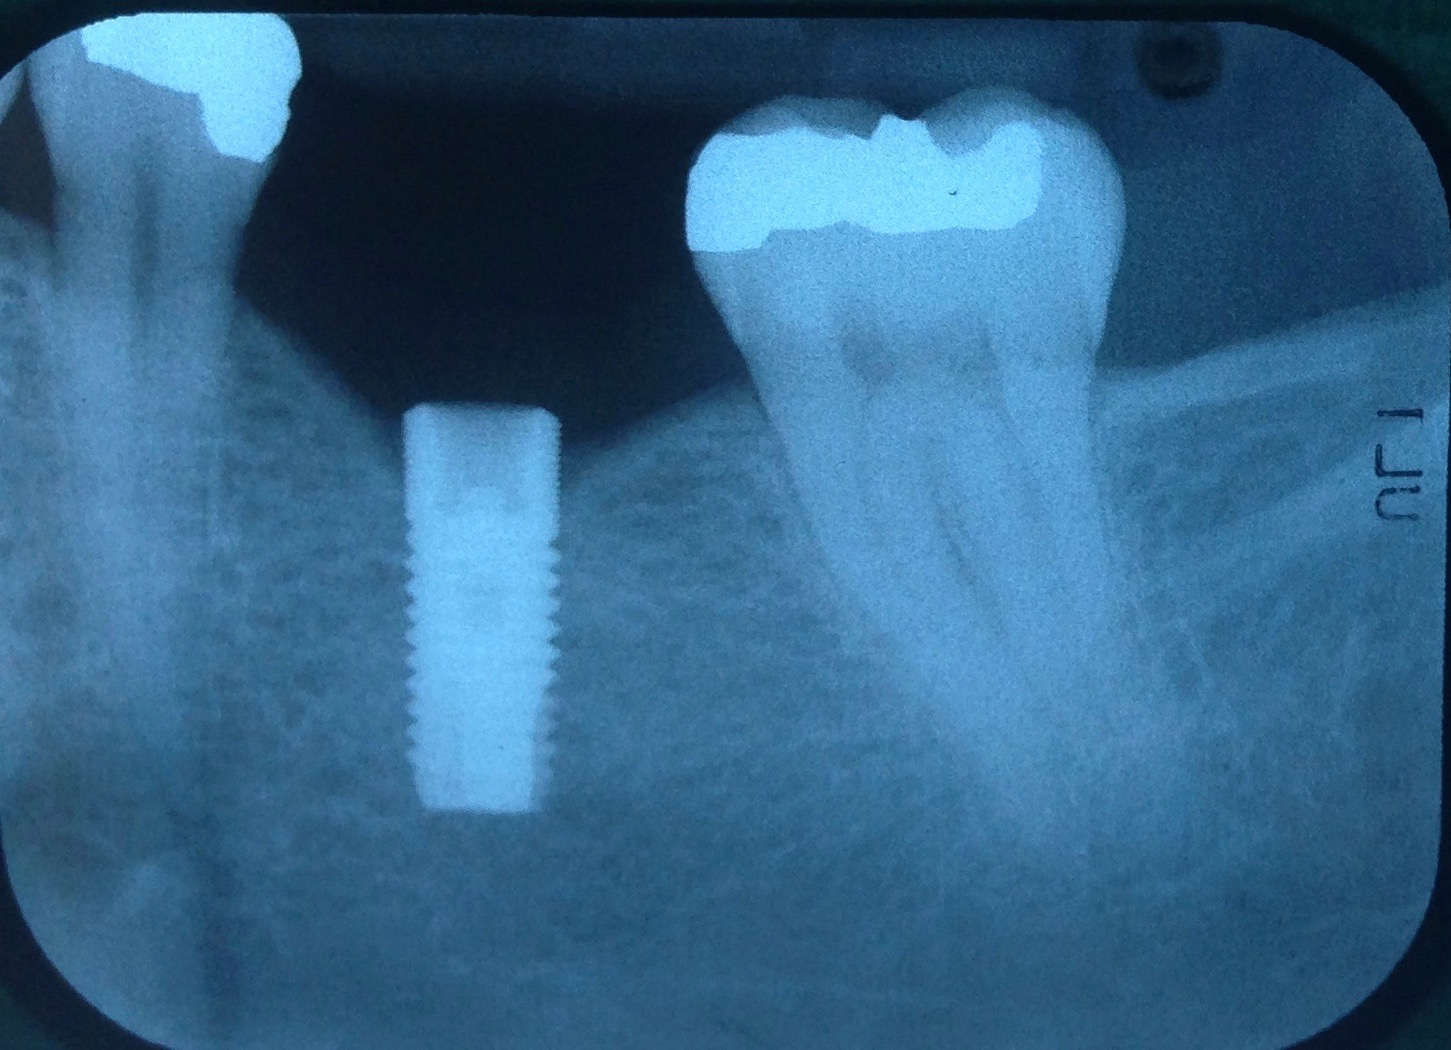

Fig 3. Fractured abutment screw.

Figure 3